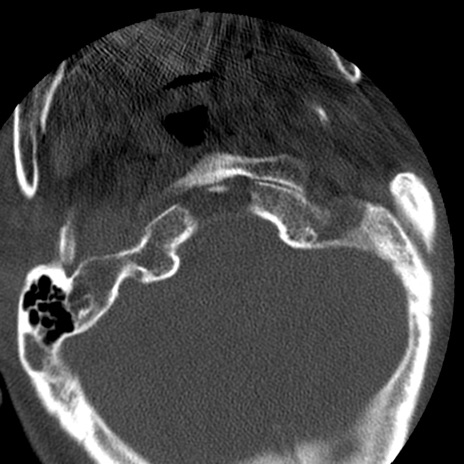

症例50 頚椎CT(横断像)

冠状断像